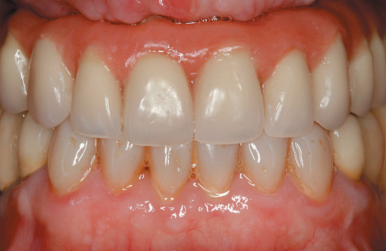

We present the clinical case of a 56-year-old female patient, who has been wearing an upper complete removable prosthesis and a lower partial prosthesis for more than 20 years. She comes for consultation requesting implant rehabilitation to replace her current prosthesis to improve her masticatory function. In the intraoral examination we can observe that the prosthesis meets quite satisfactorily the aesthetic requirements of the patient, but according to her, they move when chewing. When removing the prosthesis, a maxillary edentulous ridge with an evident centripetal resorption that has left the starting situation close to that of a skeletal class III (Figures 1 and 2).

implants that will serve to shape the provisional ones in terms of aesthetics and function before the final prosthesis (Figures 23-24).

After four months the loading of the inserted implants in this second surgical phase is carried out. Again, a second provisional prosthesis of progressive loading is chosen, elaborated in the same way as the previous ones. three months aft er the occlusion is prepared for the manufacture of the fi nal prosthesis, so the prosthesis is transformed into a metal-ceramic prosthesis, screwed on transepithelial made by CAD-CAM (Figures 25-26).

The pati ent has recovered the requested functi on, as well as the correction of the occlusion of the complete prosthesis, which presented a right lateral cross bite with decrease in the vertical dimension at the beginning of the treatment. The patient comes to her review and the treatment remains stable as shown in the images taken after 10 years of follow-up (Figures 27-28).